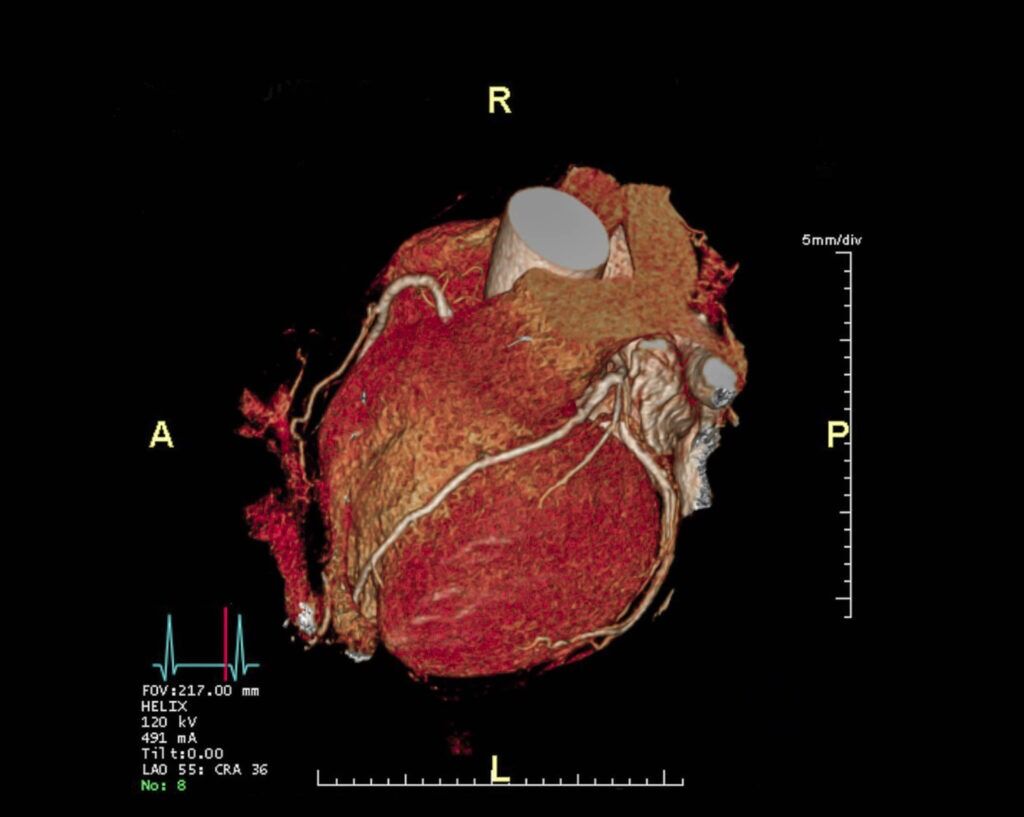

Cardiovascular Health

In the realm of cardiovascular health, diagnostic imaging continues to be a game-changer. Imaging techniques like angiography and coronary CT angiography enable cardiologists to visualize arterial blockages, aneurysms, and other heart-related issues with unprecedented precision. Recent statistics reveal that approximately 80% of cardiovascular diseases can be prevented or managed with early detection and lifestyle changes (Harvard University). The adoption of more sophisticated imaging technology has further increased the accuracy of diagnosis. There are several companies that manufacture CT Scanners that can produce these images. Popular models in the pre-owned equipment market include:

Siemens CT Scanners

- Siemens SOMATOM Definition Edge

- Siemens SOMATOM Force

- Siemens SOMATOM Definition AS

- Siemens Sensation & Sensation Open models

- Siemens Go NOW

- Siemens Perspective

GE CT Scanners

- GE Discovery CT 590 RT

- GE Discovery CT750 HD

- GE Optima 660

- GE Optima 540

- GE Revolution EVO

- GE Revolution HD

- GE LightSpeed 16

- GE BrightSpeed 16

Canon (formerly Toshiba) CT Scanners

- Canon (formerly Toshiba) Aquilion ONE / GENESIS Edition

- Canon (formerly Toshiba) Aquilion Prime

Philips CT Scanners

- Philips IQon Spectral

- Philips Brilliance & Big Bore 16 Slice

- Philips Ingenuity 64 Slice